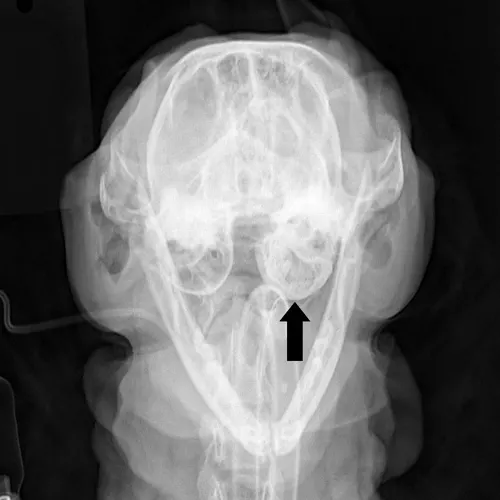

Feline inflammatory polyps are pedunculated benign fibrous masses that are infiltrated with inflammatory cells. Also known as nasopharyngeal, otopharyngeal, or middle ear polyps, these masses are most commonly found in cats younger than 2 years of age. The masses originate within the auditory tube or from the rostral aspect of the dorsolateral compartment of the tympanic bulla (Figure 1). Polyps may extend into the pharynx via the auditory tube, the external ear canal via rupture of the tympanic membrane, or both.

FIGURE 1 Ventral view of the skull demonstrating the two possible locations of inflammatory polyps: the external ear canal and nasopharynx. Courtesy Dr. Daniel A. Degner

FIGURE 2 Open-mouth radiograph of a cat with inflammatory polyps. Note the thickened bulla (arrow) compared with the contralateral normal bulla.